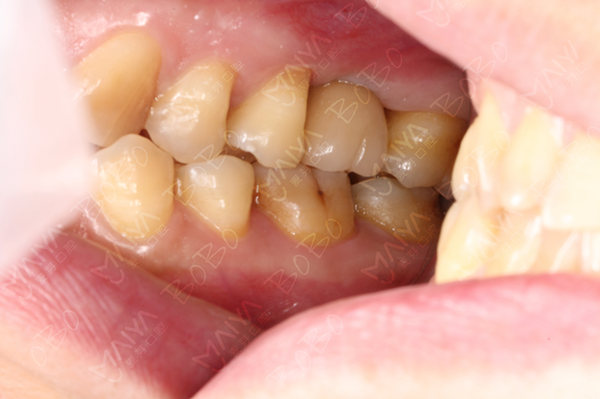

种完牙后的牙齿